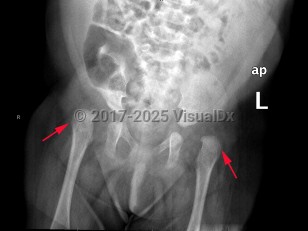

Developmental dysplasia of the hip in Child

A spectrum of developmental abnormalities of hip joint dislocation or subluxation of the acetabulum and proximal femur (head), typically diagnosed in infants and children. Most often unilateral, but may be bilateral (20%). Common signs and symptoms include hip instability, pain, limited range of motion, abnormal gait, and limping. It may be associated with breech birth, family history, or social practice of swaddling. Some neuromuscular disorders may be associated with hip dysplasia. Early intervention decreases lasting and progressive damage, limiting functional disability and preventing early-onset osteoarthritis. Many cases of infant hip instability will gradually stabilize.